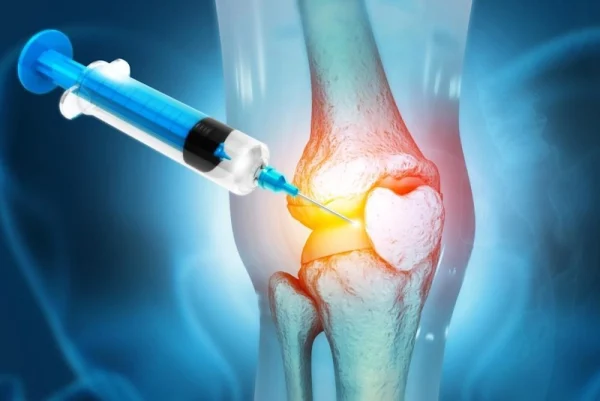

۴. درمان آسیبهای عضلانی و اسکلتی (ارتوپدی)

پلاسماتراپی در حوزه ارتوپدی و فیزیوتراپی برای تسکین دردهای مزمن کاربرد گستردهای دارد. این روش با کاهش التهاب در بافتهای نرم، برای بهبود موارد زیر استفاده میشود:

- التهاب تاندونها (تاندونیت).

- دردهای ناشی از آسیبهای ورزشی.

- کمک به بهبود آسیبدیدگیهای مفصلی و آرتروز.